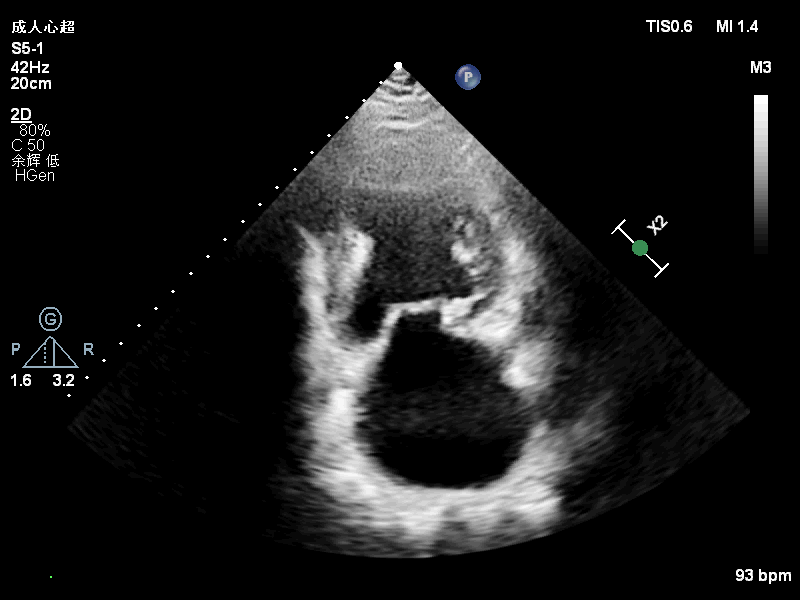

基本情况:63岁男性,患者夜间阵发性呼吸困难半年入院。患者半年前无明显诱因出现夜间平卧位呼吸困难,伴胸闷,无胸痛、大汗,无咳嗽、咳痰等,日常活动不受限。至我院住院查超声心动图提示:二尖瓣后叶P1区+前交界大脱垂,考虑DMR,Carpentier II型,二尖瓣重度关闭不全(重度,4级),左心增大,冠脉造影提示LAD近段80%狭窄,LCX远段70%狭窄,RCA近段75%狭窄,远段70%狭窄,建议患者行外科二尖瓣修复+冠脉搭桥手术治疗,患者拒绝外科手术后出院。出院后患者口服阿司匹林、螺内酯、厄贝沙坦氢氯噻嗪等药物治疗,仍有间断夜间平卧位呼吸困难,为进一步诊治收入院。

入院诊断:心脏瓣膜病,原发性二尖瓣关闭不全,二尖瓣后叶及交界区脱垂 二尖瓣重度关闭不全, 冠状动脉粥样硬化性心脏病, 劳力+自发型心绞痛,心脏扩大,心功能III级(NYHA),高血压,高脂血症